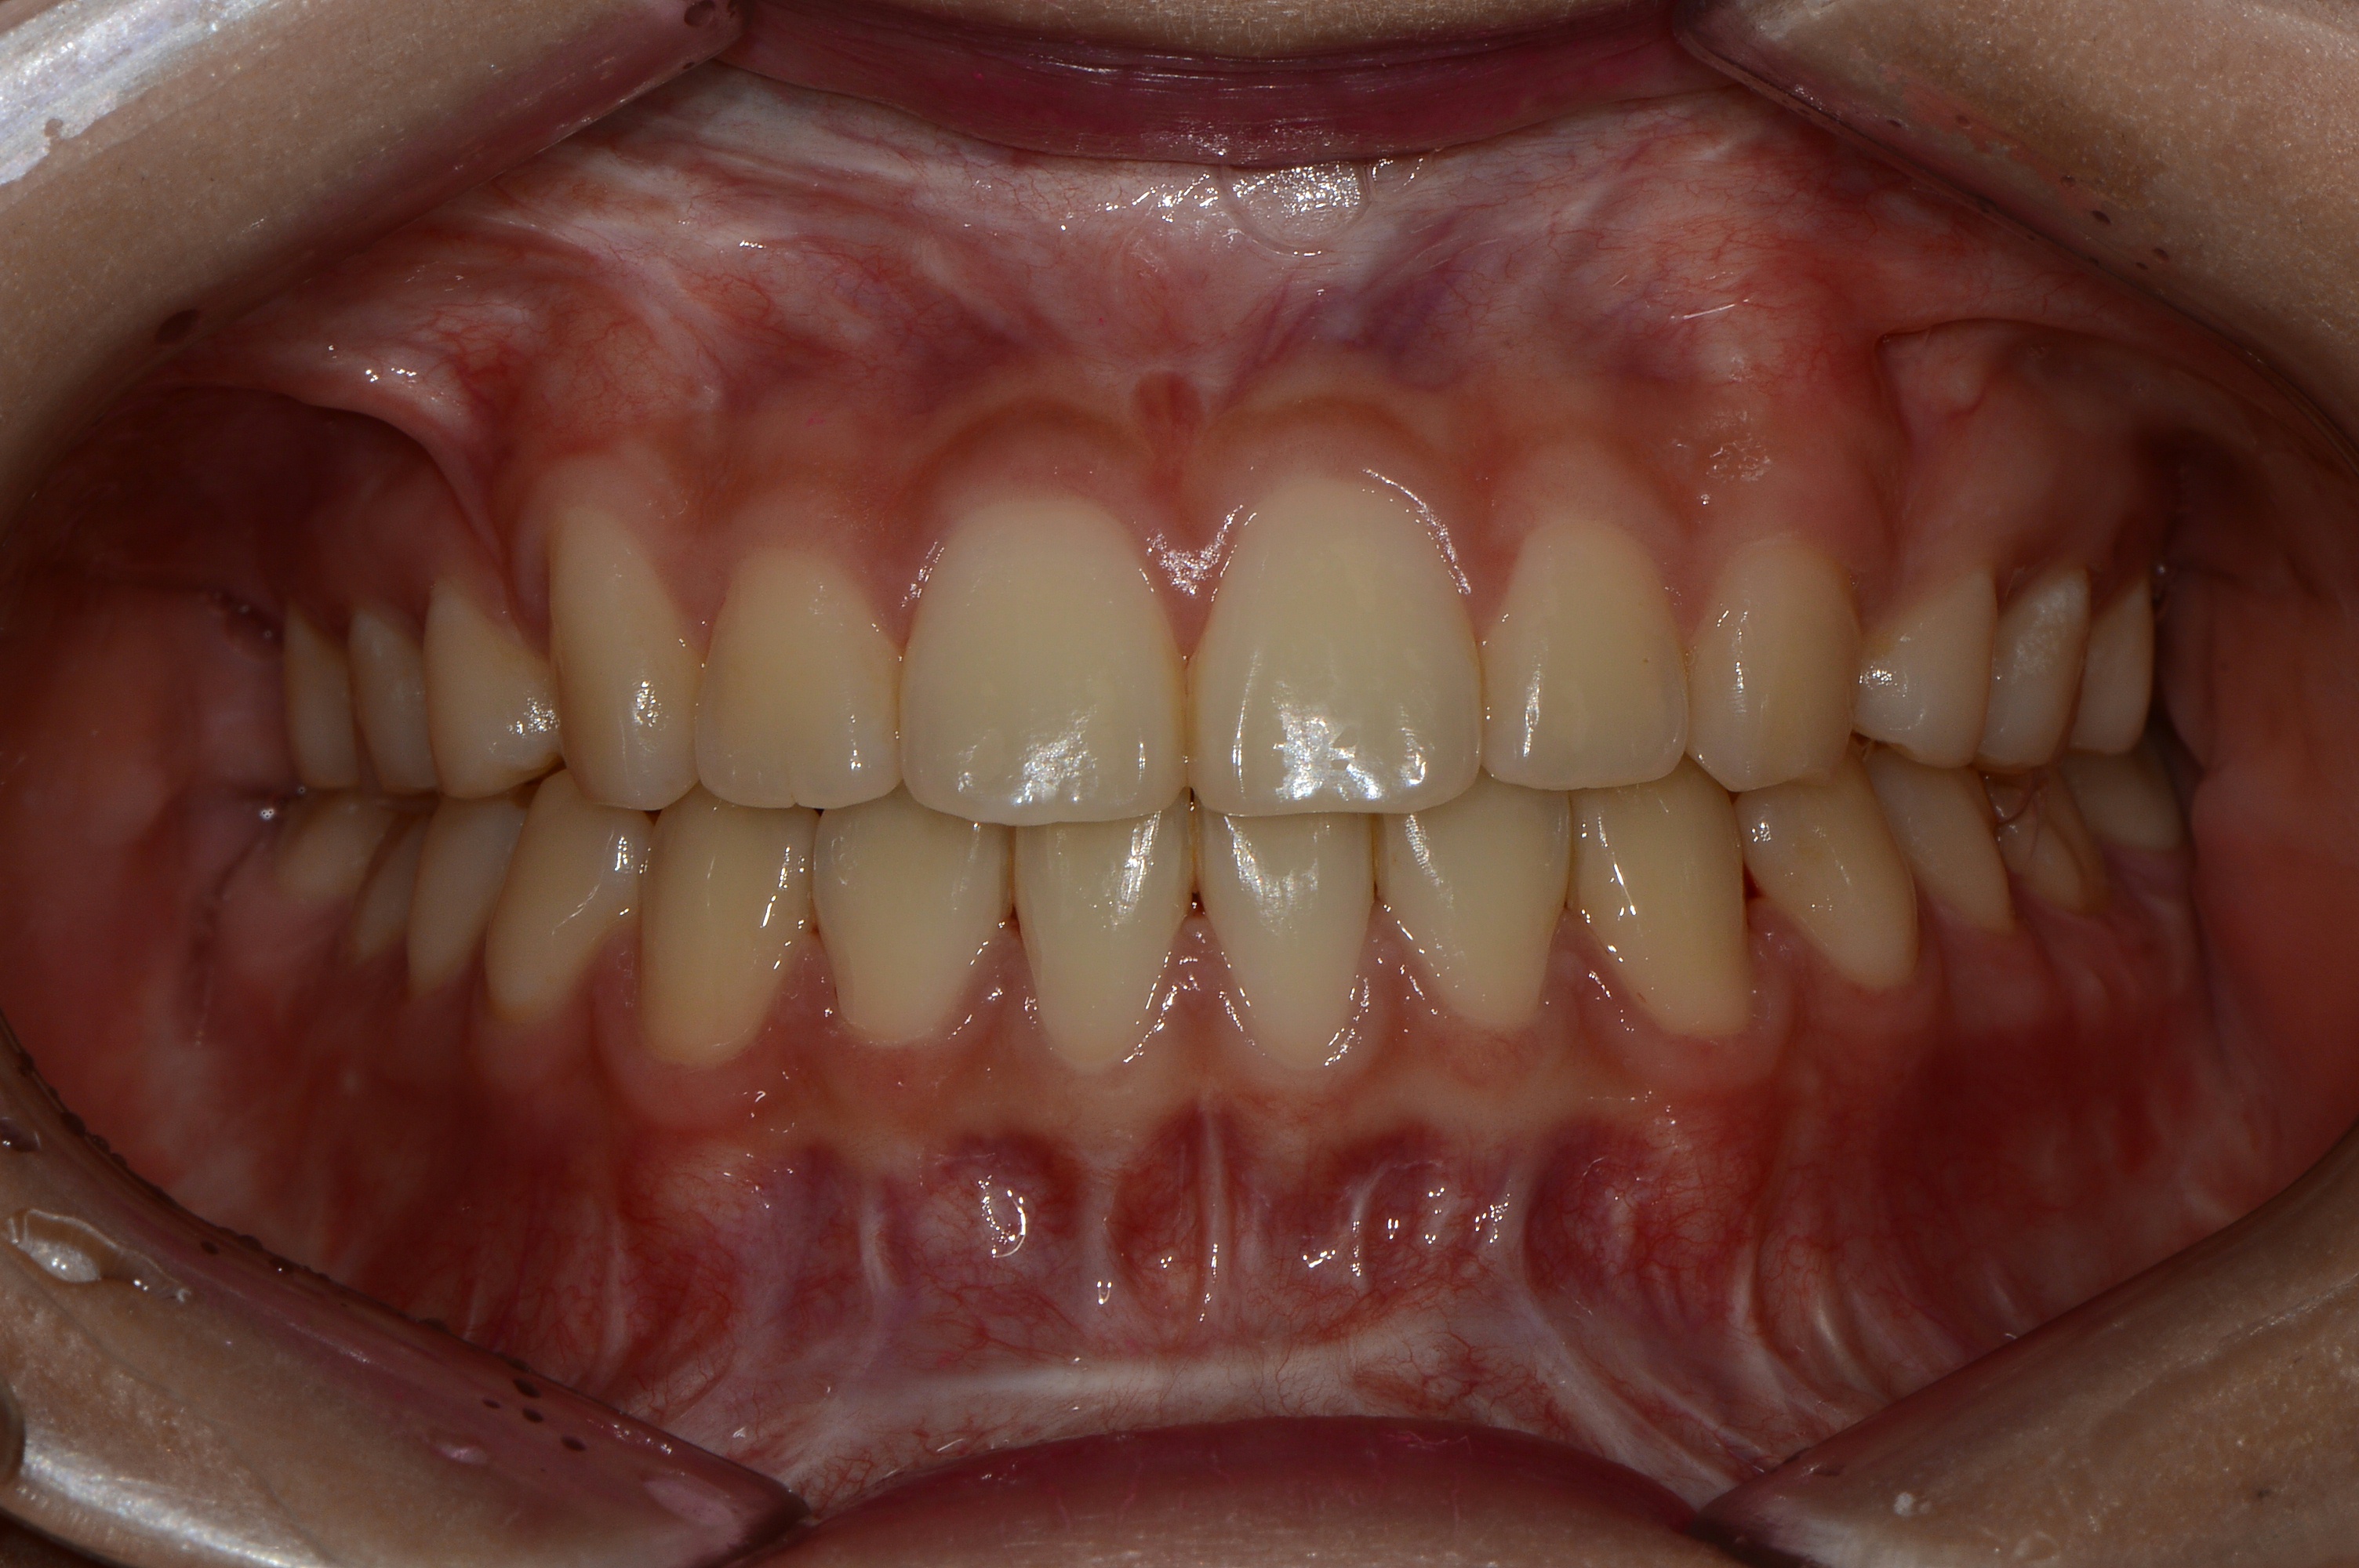

치료 전 사진입니다.